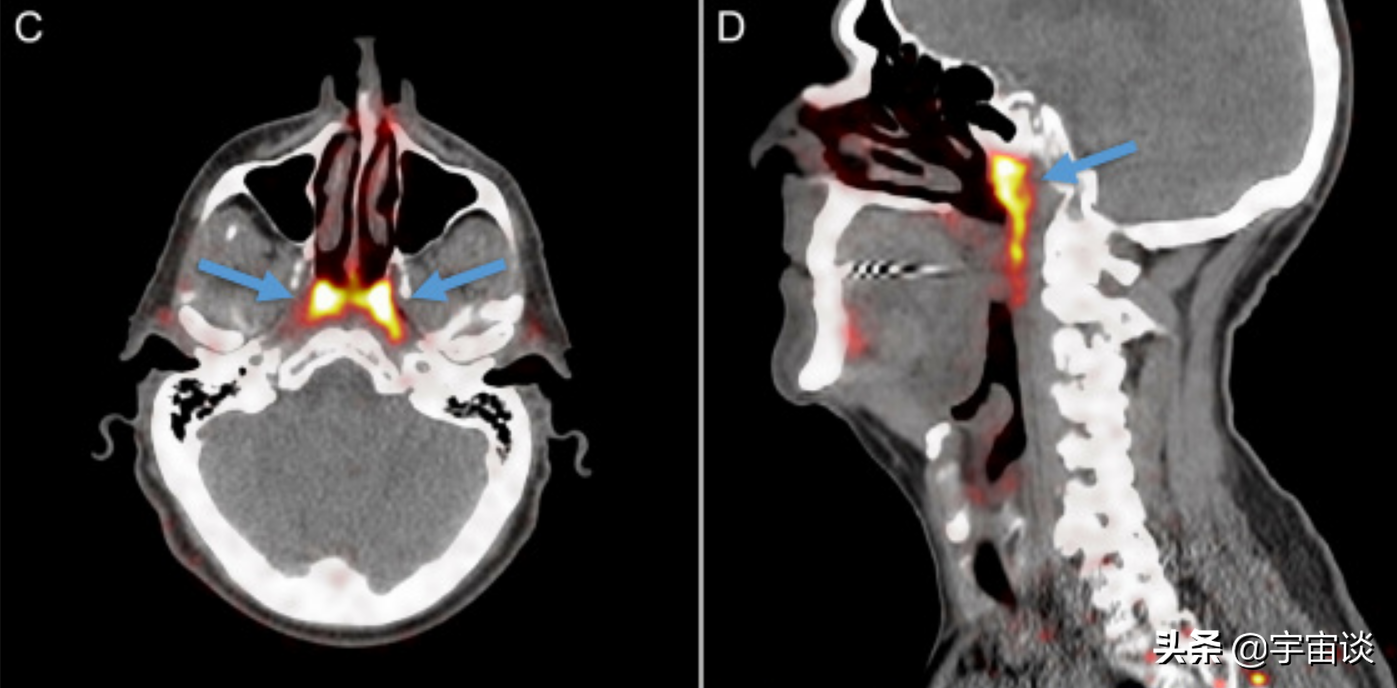

原來這個研究小組最開始的時候並不是來研究唾液腺和人體結構的,而是研究前列腺癌的,在無意當中發現了這個特殊的器官,並且把它命名為管狀腺。當然發現之後研究小組也隨後對很多人進行了比對,發現這並非是某些人群特有,而是人類都普遍存在的一個器官。這也正是說明了這個器官是人類的標配。而研究小組經過研究後又有了新的發現:這個器官或許對治療癌症有著很大的幫助,尤其是對於一些頭頸部有癌症的患者來說。這又是怎麼一回事呢?

隨後研究小組也對病人進行了分析,從以往的接受放療的病人數據來看,對這個部位放療的越多,併發症也就越來越嚴重,而這個新器官的發現,對於癌症患者來說是一個非常大的好處,畢竟在以後的治療上,能夠避免這個新發現區域的輻射,或許就能夠降低併發症,提高治療的成功率。